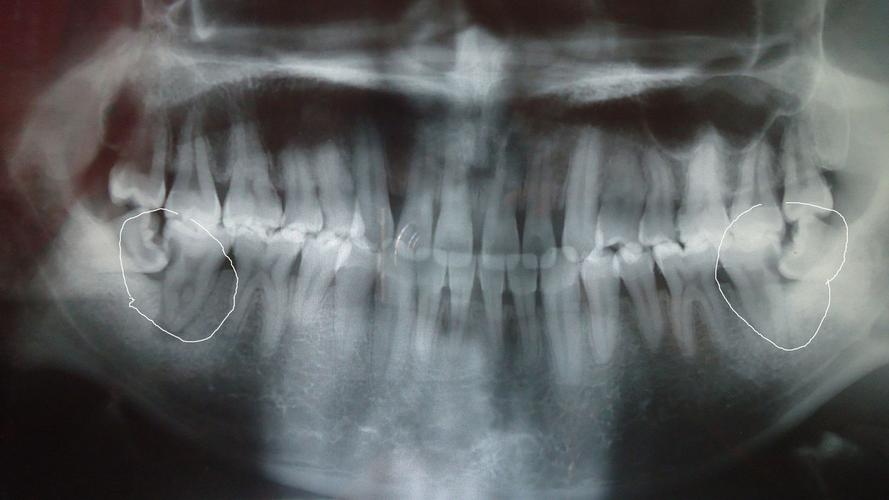

根尖炎症状,牙根尖周炎晚期图片

x线片显示根尖部局限性的不透射影像.无自觉症状,勿需治疗.

根尖周炎的牙片图

慢性根尖炎图片

根尖周炎图片

根尖有炎症的牙片图

慢性根尖周炎图片

根尖周炎症状图片

根尖周炎的症状图片